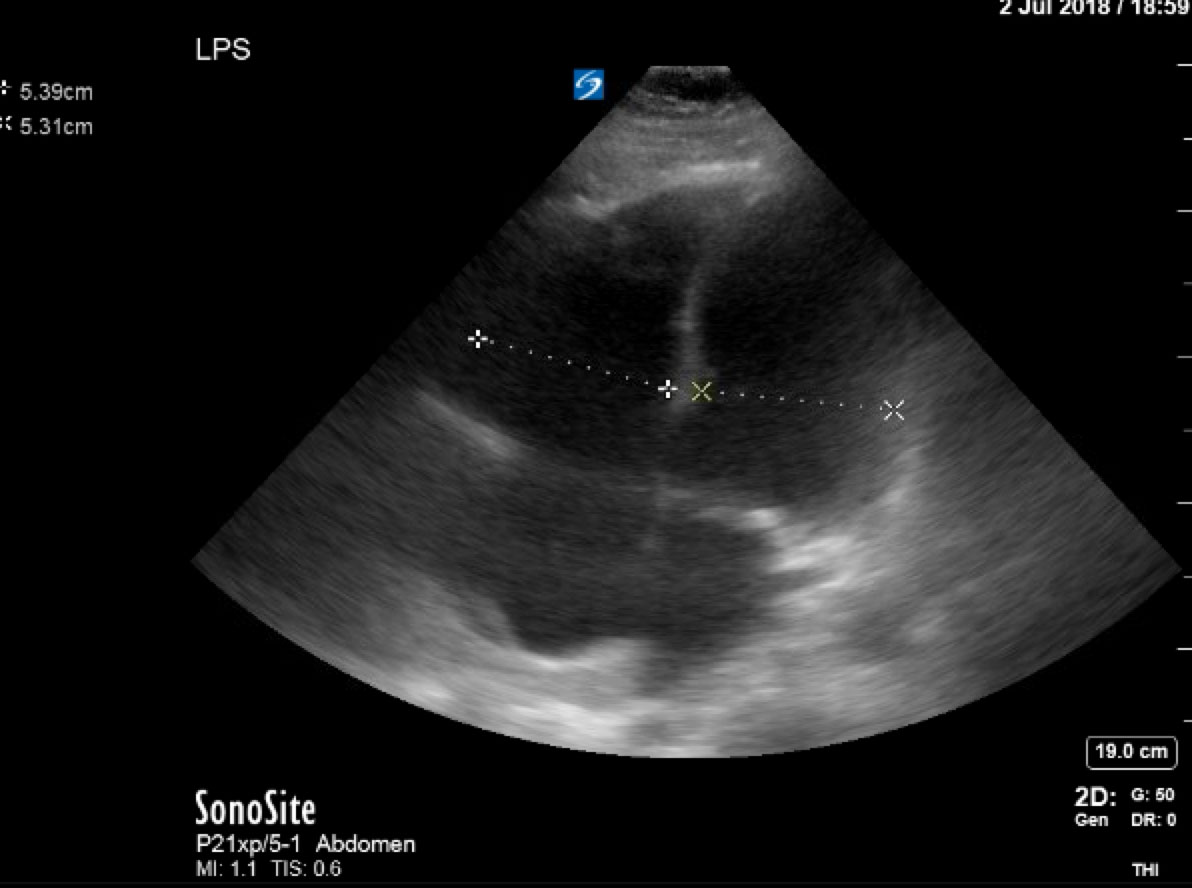

A 46 year old male with a cast on his left leg from an ankle fracture presents to the ED complaining of pleuritic chest pain and shortness of breath. The team will take a history and start workup when the patient will suddenly state he’s “not feeling well” and then arrest. The team will perform ACLS consistent with the PEA algorithm and should consider IV thrombolytics. If IV thrombolytics are administered, the patient will have ROSC.